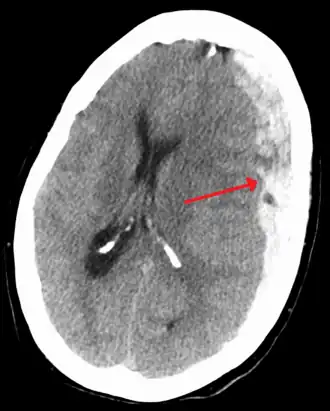

Subdural hematoma as marked by the arrow with significant midline shift | |

On a CT scan, subdural hematomas are classically crescent-shaped, with a concave surface away from the skull. However, they can have a convex appearance, especially in the early stages of bleeding. This may cause difficulty in distinguishing between subdural and epidural hemorrhages. A more reliable indicator of subdural hemorrhage is its involvement of a larger portion of the cerebral hemisphere. Subdural blood can also be seen as a layering density along the tentorium cerebelli. This can be a chronic, stable process, since the feeding system is low-pressure. In such cases, subtle signs of bleeding—such as effacement of sulci or medial displacement of the junction between gray matter and white matter—may be apparent.